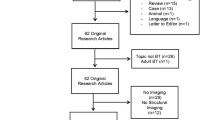

Thirty-five survivors and 56 healthy controls underwent neuroimaging and completed a measure of oral processing speed. The survivor group was further divided based on treatment (i.e., chemoradiation therapy (n = 20) vs. surgery only (n = 15)) to better understand the impact of treatment.